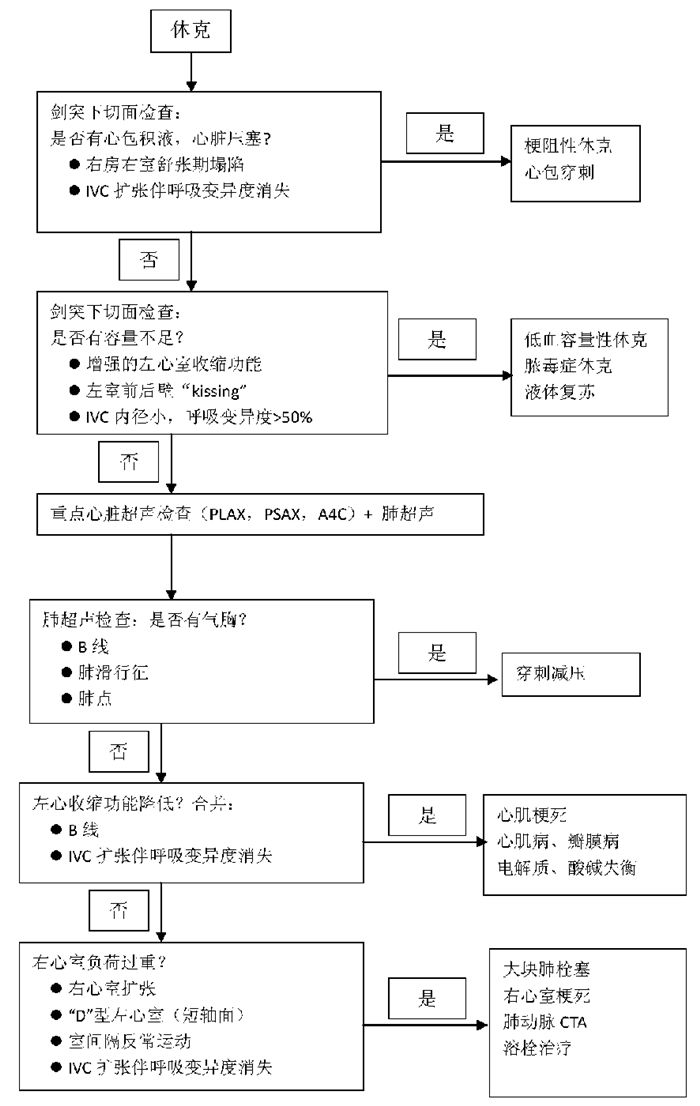

(3)改良休克超声检查流程[25]:结合国外的流程草案,简化休克诊断处理流程如下(图 36)。

| 图 36 简化休克诊断处理流程 |